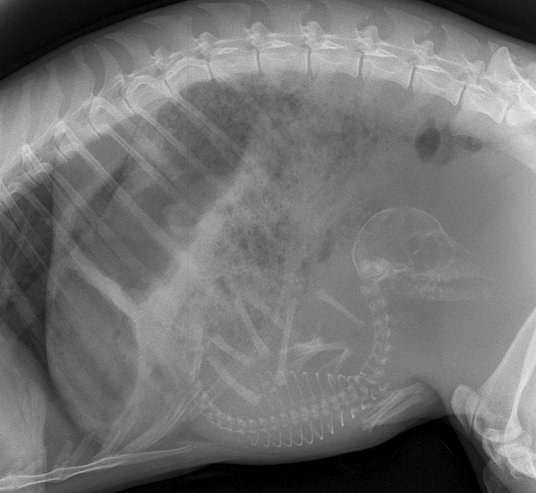

▼怀孕的猫咪